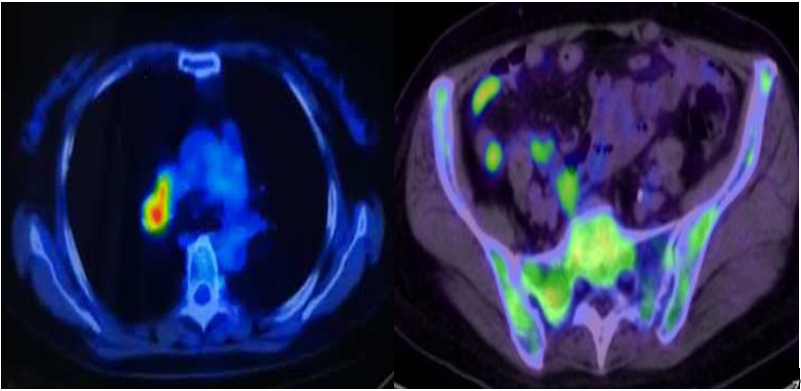

右肺上叶多发结节(2.3*2.0*2.1cm),周围伴多发磨玻璃密度灶,跨叶尖裂生长,代谢异常增高,考虑恶性;

-

右侧肺门及纵隔内(血管前,气管前,隆突下)多发肿大淋巴结,代谢异常增高,考虑恶性。

双侧髂骨PET-CT显像可见放射性浓聚,考虑转移。